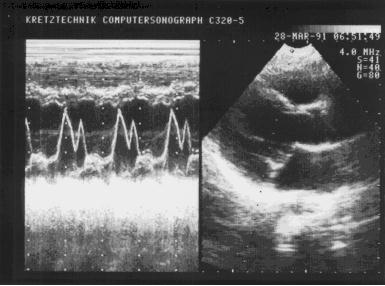

При М-модальном сканировании видно, что движение нормального митрального клапана отражает все фазы диастолического наполнения левого желудочка (рис. 1). Во время систолы желудочков (интервал С-Д) весь клапан смещается вперед из-за движения в этом направлении митрального кольца. В фазу быстрого наполнения передняя створка открывается с достаточно большой скоростью и движется вверх к датчику (интервал Д-Е). В середине диастолы, во время медленного наполнения левого желудочка и повышения в нем давления, створка клапана прикрывается, удаляясь от датчика (интервал Е-F). В систолу предсердий она снова быстро открывается (F-А) и с началом его систолы вновь закрывается (А-С). Таким образом, форма движения передней створки митрального клапана во время диастолы напоминает букву М. Задняя митральная створка совершает подобное движение в противоположном направлении, но с меньшей амплитудой, и по своей форме напоминает букву W. Нередко при открытом клапане она сливается с нижележащими структурами и не всегда четко лоцируется.

Рис. 2. М-эхограмма нормального митрального клапана (собственное наблюдение).